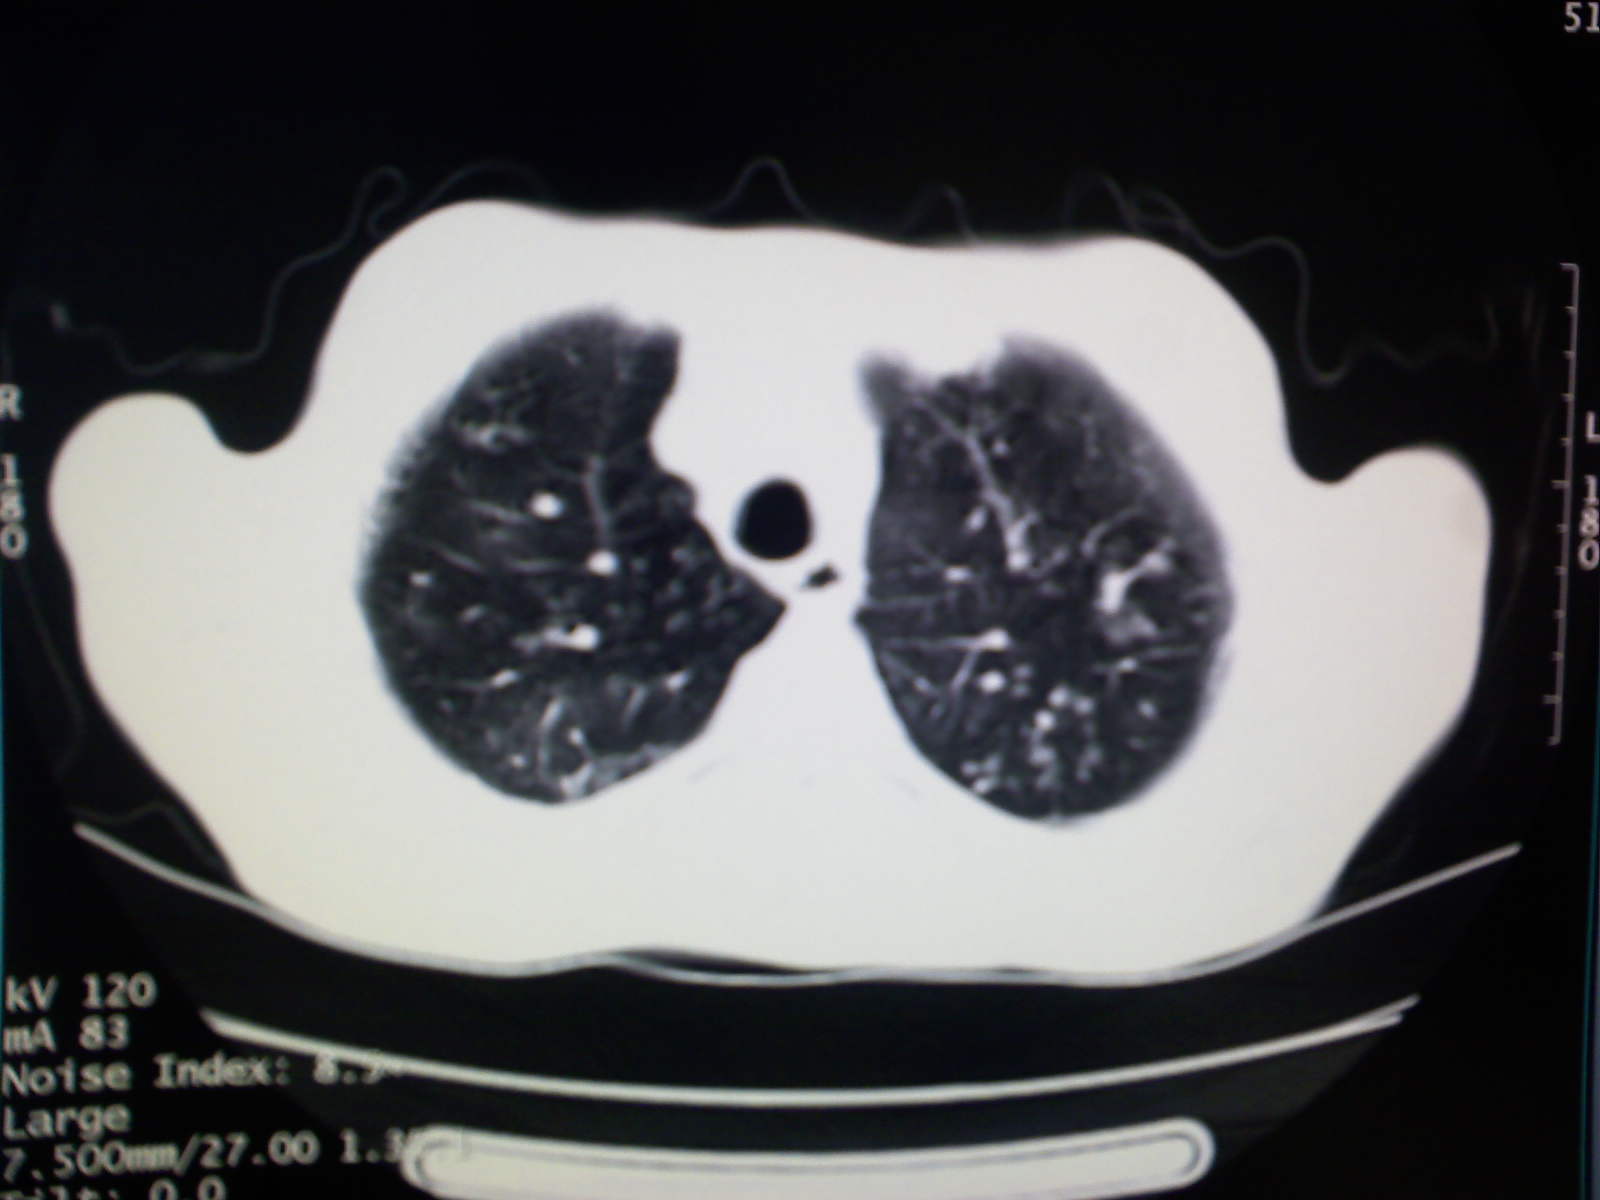

以下是引用卜一在2009-4-11 15:50:00的发言:[br]双肺继发性肺结核伴空洞形成,不排除合并霉菌感染!(病灶呈多形态 多特征 散在分布)。另:合并支气管扩张征伴感染!

以下是引用主力军在2009-4-11 15:55:00的发言:[br]两肺继发性肺结核可能性大。

以下是引用康鹏在2009-4-11 16:30:00的发言:[br]双肺继发性肺结核伴空洞形成合并感染[br]支气管扩张合并感染